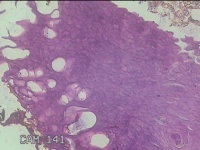

左大拇指红色赘生物

性别

男

年龄

75岁

临床诊断

病毒性疣?

一般病史

灰白粉红色肿物0.5x0.3x0.2cm一个,表面糜烂。

标本名称

大体所见

左大拇指起红色赘生物1年。

图1

皮角